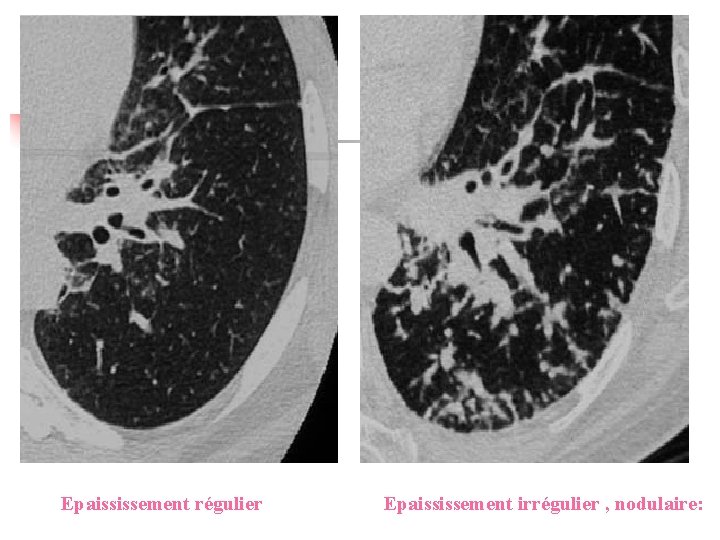

Morphologie : Ø Ø Lignes brisés déssinant des polygones complets ou non , centrés par l’artére centrolobulaire. Épaisissment périlobulaire : régulier, irrégulier nodulaire ou spiculé, calcifié.

Epaississement régulier Epaississement irrégulier , nodulaire: